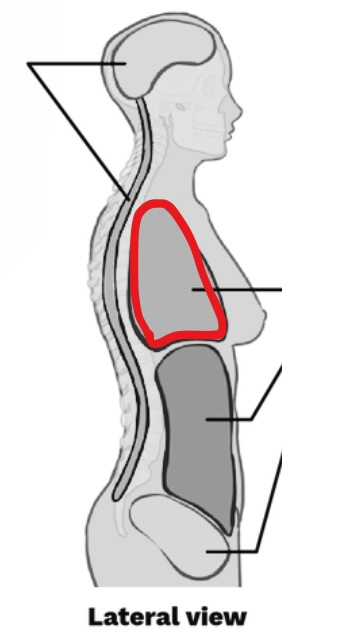

What Cavity is this?

Thoracic cavity